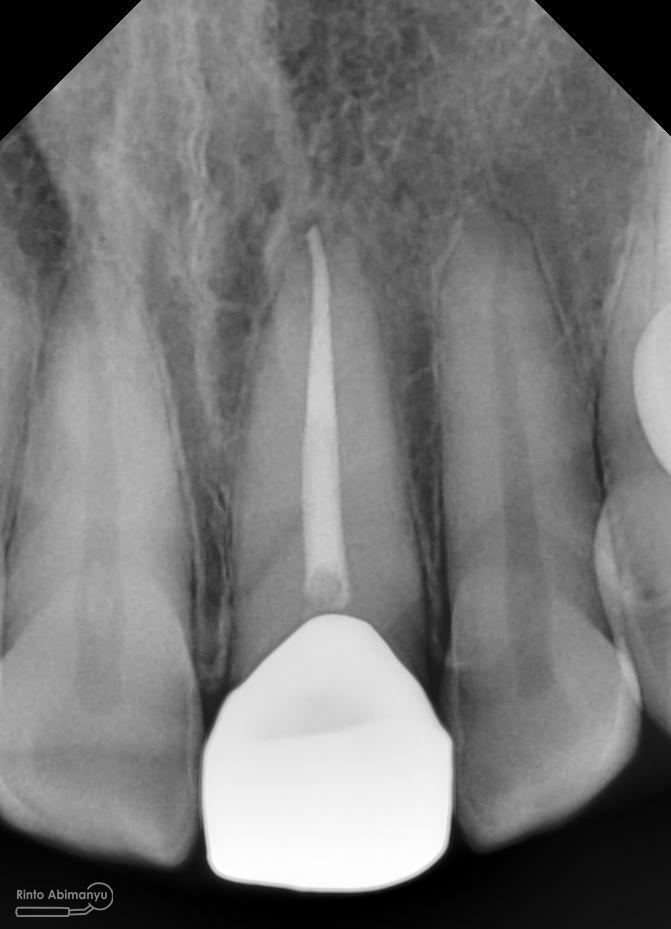

Foto radiografis trial guttap gigi 22

Nah dari foto ronsen ini juga saya melakukan evaluasi hasil pengisian pada gigi 11 21 nya… alhamdulillah pengisian yang kemarin terlihat sepanjang kerja dan padat serta rapat… Pada gigi 22 nya pun pengepasan guttap terlihat sudah sepanjang kerja…